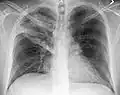

AP CXR showing left lower lobe pneumonia associated with a small left sided pleural effusion

AP CXR showing right lower lobe pneumonia

AP CXR showing pneumonia of the lingula of the left lung